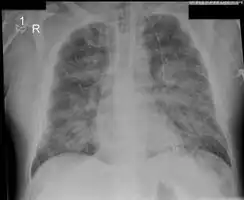

X-Ray showing pulmonary oedema

Low oxygen saturation and disturbed arterial blood gas readings support the proposed diagnosis by suggesting a pulmonary shunt. A chest X-ray will show fluid in the alveolar walls, Kerley B lines, increased vascular shadowing in a classical batwing peri-hilum pattern, upper lobe diversion (increased blood flow to the superior parts of the lung), and possibly pleural effusions. In contrast, patchy alveolar infiltrates are more typically associated with noncardiogenic edema[8]